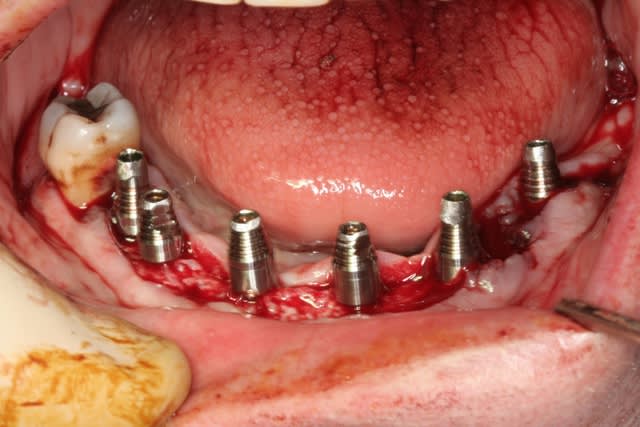

bon, et bien c'est fait!

durée...de 9h30 à 17h30...çà c'est assez épuisant...

comme promis, et avec la bénédiction de posit, voici quelques morceaux choisis de cette journée...

ne me dites pas que les vis d'ostéosynthèses sont pas vissées à fond...c'était le "grain de sable" de la journée, vis commandées par posit, mais pas les bonnes livrées...donc système D car tournevis inutilisable

heureusement, les guides sont "superlatifs": quelle précision d'ajustement osseux!!! à tel point qu'au maxillaire on aurait bien pu totalement se passer des vis d'ostéosysthèse...

ah, oui, j'allais oublier au maxillaire 8 legacy3 diamètre 3.7mm et en 13 de long (sauf 22 en 11.5mm)

mandibule 6 implants de 13mm et 3.7mm de diamètres (sauf 36 et 45 en 4.2mm/13)